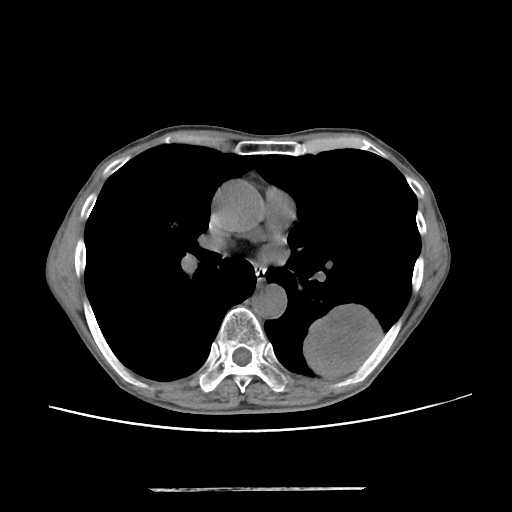

CT検査

内科領域

胸部

肺がん

肺炎